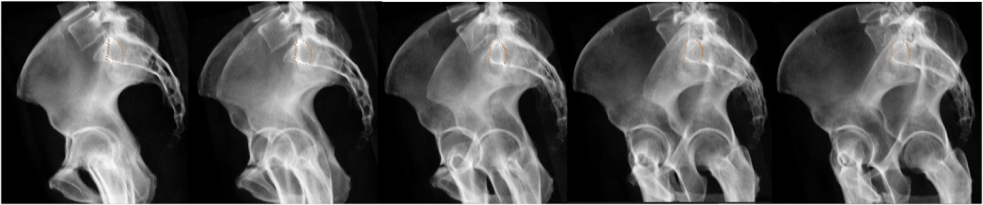

图1所示。1例8岁道路交通事故后左侧c型骨盆骨折S1关节分离的患者,“骶髂向融合术”术前3D图像规划:3D图像(a)转化为2D融合图像(b)。理想螺钉位置规划(c)及椎弓根S1前后边界标记。融合图像在一个真正的横向(e)和“骶髂”的方向通道轴视图。

图2所示。序列的旋转融合图像(a)从真正的侧到“骶髂”走廊。我们旋转图像,直到椎弓根中心的中心点和S1体中心重叠。